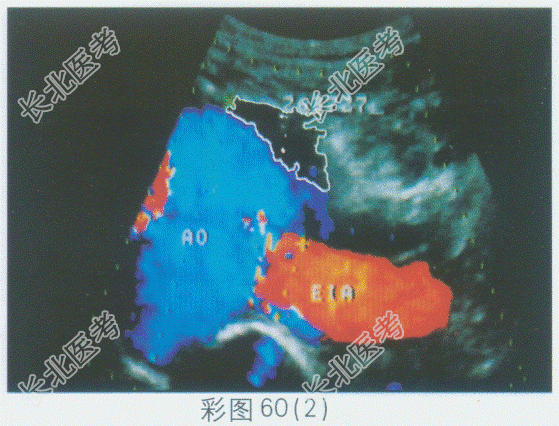

- 单项选择题临床资料:女性患者, 39岁。无意中发现腹部包块半年,肿块进行性增大并腰酸、双下肢酸痛, 加重气短左下肢水肿1周。

临床物理检查:左上腹膨隆, 触及一约15.0cm×20.0cm肿物,边界清楚, 活动度差,有明显膨胀性搏动感及震颤, 无触压痛及反跳痛;听诊有明显血管杂音, 与脉搏节律一致。

超声综合描述:腹主动脉失常态, 起始段内径1.7cm,腹腔动脉干水平内径1.6cm, 自肠系膜上动脉水平至髂总动脉分叉处明显增宽,最大内径11.3cm, 增宽段显示长度17.0cm;PW: 呈动脉充填型湍流频谱,V~116.0cm/s; 瘤样扩张近心端呈S形屈曲,CDFI: 呈明亮高速五彩镶嵌状血流束,V

261.9cm/s。见彩图60。